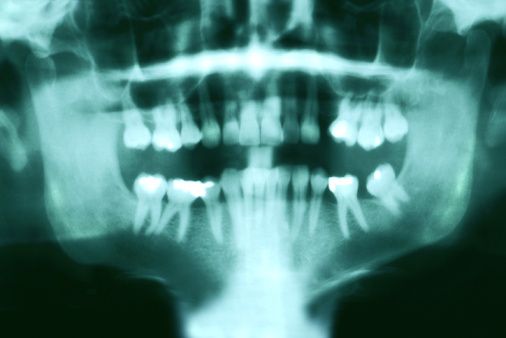

flikr/ Assure a Smile / Dental x-ray

Сначала они съездили в одну лабораторию, расположенную в Борленге ( Borlänge), для того, чтобы сделать рентгеноскопию зубов мудрости. Потом вернулись обратно в Сеффле и отправились в Вестерос (Västerås), чтобы пройти МРТ коленных суставов. В общей сложности за 18 часов они проехали более 1 000 километров.

В соседней Норвегии национальное Медицинское общество признало практику установления возраста беженцев с помощью рентгена челюстей неэтичной .

После этого университет Осло не стал продлевать контракт с государством на проведение рентгеноскопии челюстей просителей убежища, по которому за предыдущие два года заработал 14 млн крон (€1.6 млн; $1.65 млн), сделав более 3 500 экспертиз.